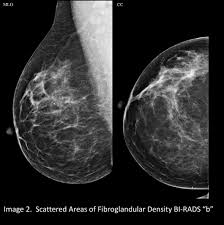

What Does Breast Cancer Look Like On A 3D Mammogram : Mammography 3d Mammography Tomosynthesis Densebreast Info Inc : Macrocalcifications, which look like small white dots on a mammogram.. To license this video for patient education or content marketing, visit: The doctor reading your mammogram will be looking for different types of breast changes, such as small white spots called calcifications, larger abnormal areas called masses, and other suspicious areas that could be signs of cancer. This overlapping tissue can cause the resulting image to look like cancer. Microcalcifications, which look like white specks on a mammogram. The tumor cells don't stay within the clear borders of the mass, but instead invade the nearby breast tissue.

Essentially, mammograms turn a 3d object into a 2d object. This is why you should always talk to your doctor if you notice an unexplained change in the size of a breast. What does the doctor look for on a mammogram? cancer.org. A screening mammogram is performed at regular intervals to check for breast cancer in women who have no signs or symptoms of the disease. Bright spots on a mammogram that look like potential tumors could turn out to be overlapping tissues or a blood vessel folding over on itself, friedewald said. To license this video for patient education or content marketing, visit: What does breast cancer look like? This overlapping tissue can cause the resulting image to look like cancer. Finding breast lumps and seeing change in the size and shape. Screening mammograms have been used since the 1980s. Digital breast tomosynthesis (tomo), also known as 3d mammography, is a revolutionary new screening and diagnostic breast imaging tool to improve the early detection of breast cancer. Ultrasound characterization of breast masses. indian journal of radiology and imaging. Calcifications are calcium deposits within the breast tissue and they look like small white spots.

Moose & doc breast cancer, 21 may 2018. We'll show you breast cancer pictures to help you identify any physical traits of the condition. Normal breast tissue can look 100,000 different ways on a mammogram. Finding breast lumps and seeing change in the size and shape. Dense breast tissue appears solid. Essentially, mammograms turn a 3d object into a 2d object. American cancer society, 9 oct 2017. That makes it easy to detect abnormalities, which generally show up as white. A 3d mammogram is used to look for breast cancer in people who have no signs or symptoms. More importantly, the overlap can obscure small breast cancers. A screening mammogram is performed at regular intervals to check for breast cancer in women who have no signs or symptoms of the disease. Several patterns of calcifications are seen with dcis, including: Breast cancer and some noncancerous (benign) breast conditions can appear white on a mammogram.